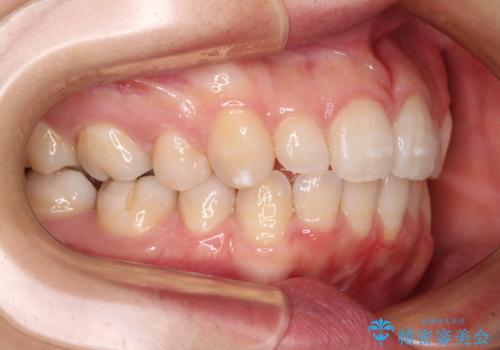

抜歯矯正の後戻り インビザライン・ライトによる矯正治療

治療途中、妊娠・出産があり、1年近く治療が停滞しましたが、無事に終了することができました。

インビザライン・ライトは提供されるマウスピースの数に制限があり、通常のタイプよりもマウスピース提供期間が短くなっている一方、安価に治療を行うことができるプランです。

治療のゴールも変更できないため、軽微な歯列不正や、後戻り改善などに適しています。